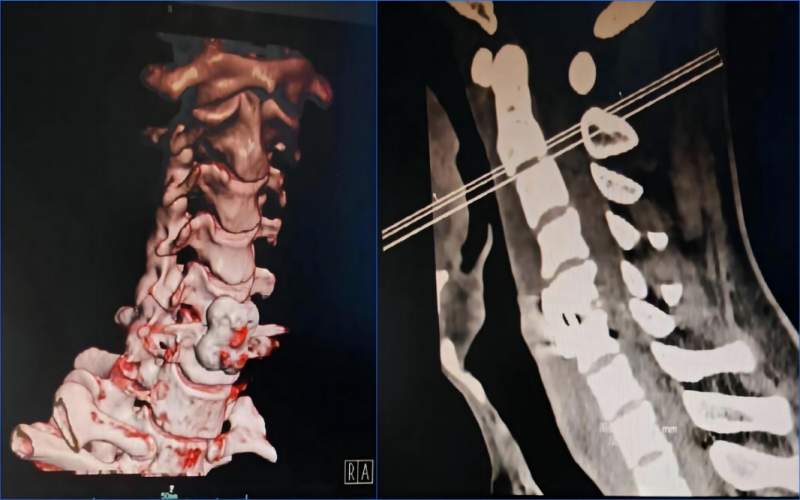

3月16日,我院脊柱骨科在蘭大二院羅志強教授指導下成功開展一例頸5-6椎間盤突出頸椎前路椎間盤切除減壓椎間盤融合術(ACDF),手術過程順利?;颊咝g后24小時后下地行走,雙上肢疼痛麻木乏力、下肢無力癥狀完全消失。此例手術是我院首例頸椎(ACDF)手術,標志著脊柱骨科又一次取得了新進展、新突破。 患者王某,男,37歲,3月6日因車禍傷致頸部、胸部疼痛,伴四肢麻木、無力,活動受限。入院后完善相關檢查,影像學檢查回報提示:頸椎生理曲度變直,頸4-6椎體邊緣骨質增生變尖,頸4/5、頸5/6椎間盤向后突出,相應硬膜囊受壓,骨性椎管前后徑見。結合病史、查體,診斷:1.頸部脊髓功能損傷C6;2.頸部脊髓水腫;3.頸椎間盤突出;4.頸椎退行性病變;5.全身多處軟組織損傷 手術采取全麻仰臥位,歷時2小時順利結束,術后患者清醒后即刻感覺雙上肢疼痛麻木乏力癥狀好轉。復查見椎體后緣骨贅磨除徹底,減壓充分?;颊呒凹覍賹κ中g非常滿意,感慨地說:“感謝酒泉市中醫(yī)醫(yī)院脊柱骨科團隊為我們患者提供了精準、安全、有效的治療方法。” ACDF是治療頸椎疾病的經(jīng)典術式,經(jīng)過臨床廣泛應用,其療效顯著,具有創(chuàng)傷小、出血少、并發(fā)癥少等優(yōu)點。與后路手術相比,前路手術可以直接解除來自脊髓前方的壓迫因素,如退變的椎間盤組織、椎體后緣骨贅、肥厚或骨化的后縱韌帶以及增生的鉤椎關節(jié)等;椎間隙植骨可有效恢復椎間隙高度、維持頸椎生理彎曲度、重建病變節(jié)段的穩(wěn)定性,符合頸椎的病理生理特點,一直是治療頸椎疾患的主流術式。 隨著微創(chuàng)理念的深化,微創(chuàng)技術的不斷進步,我院脊柱骨科堅持團結奮進、守正創(chuàng)新,圍繞“脊柱手術精細化、微創(chuàng)化”的發(fā)展思路,秉承術后加速康復理念,堅持創(chuàng)新和發(fā)展,在脊柱微創(chuàng)治療領域方面積累了豐富的臨床診療經(jīng)驗,不斷創(chuàng)新和挑戰(zhàn),以精湛的技術,造福廣大脊柱疾病患者。 脊柱骨科 就診地址:酒泉市中醫(yī)醫(yī)院四樓脊柱骨科 咨詢電話: 一樓門診部:0937-2669161